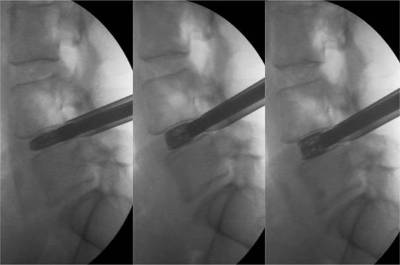

Inserción y abordaje minimamente invasivocon instrumentos de 10-12 mm de diámetro

Implante expandible hasta 14 mm de altura para restaurar la altura original de un disco degenerado y colapsado